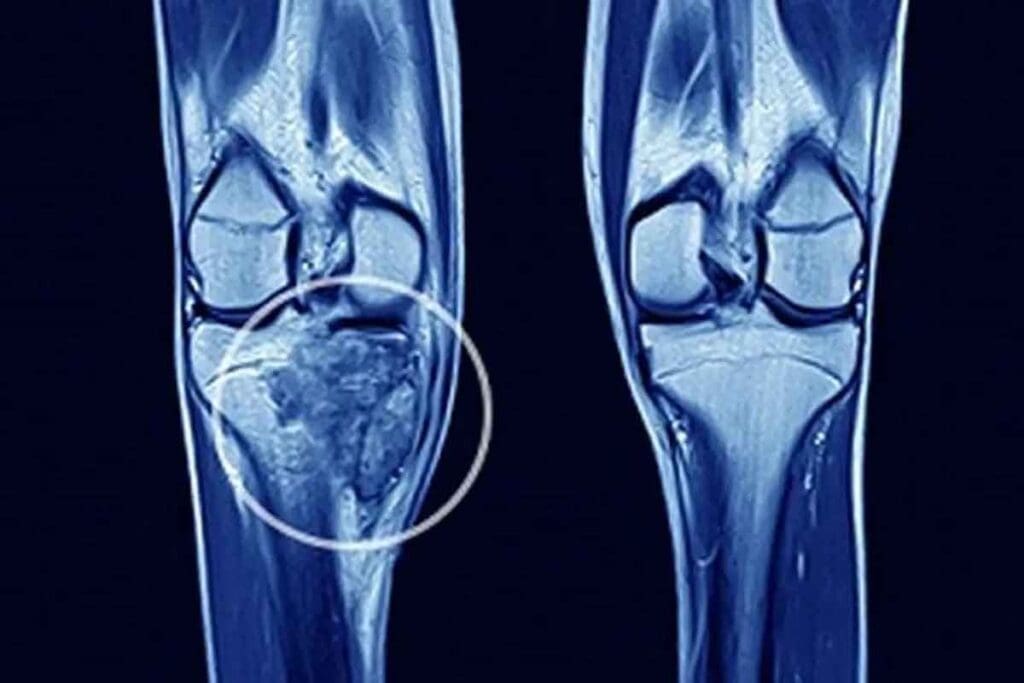

Accurate diagnosis of Ewing’s Sarcoma is key. It requires a detailed workup. This includes clinical evaluation, imaging studies, biopsy, and molecular testing. These steps help confirm the presence of this aggressive cancer.

Imaging studies are vital for diagnosing Ewing’s Sarcoma. Magnetic Resonance Imaging (MRI) is often used to see the tumor’s size and location. Computed Tomography (CT) scans check for bone involvement and metastases. Positron Emission Tomography (PET) scans show the tumor’s metabolic activity and distant metastases.

The diagnostic process for Ewing’s Sarcoma combines clinical, imaging, and molecular findings. This ensures accurate diagnosis and proper treatment planning.